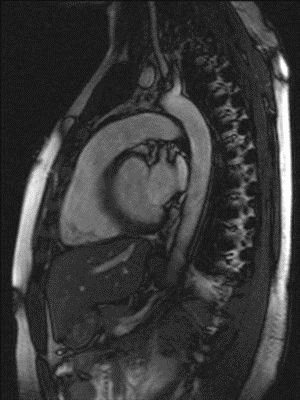

MRT-Aufnahme eines schlagenden Herzens 2, GIF-Animation

Big Bang 8

Link

GIF

MRT-Aufnahme eines schlagenden Herzens 1, GIF-Animation

Herzschlag im Kernspintomographen, GIF-Animation